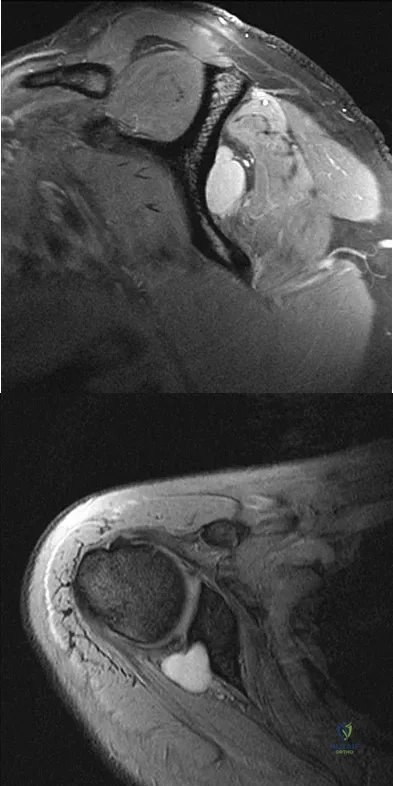

Question 76

A 25-year-old tennis player has shoulder pain and weakness to external rotation. MRI scans are shown in Figures 16a and 16b. What is the most likely cause of his weakness?

Explanation